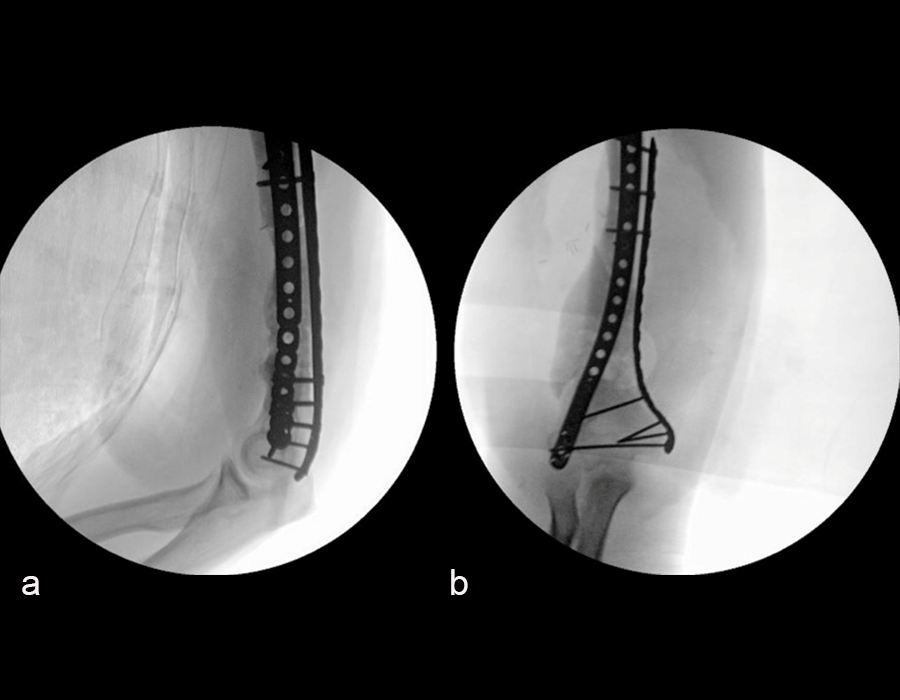

In a first stage, the distal humerus was debrided and devitalized bone was resected, leaving an 8cm defect into which a cement spacer was placed. New plates were inserted to stabilize the fracture (Fig 17 and Fig 18). Cultures taken in the OR were negative.

The second stage of surgery took place in October 2022. The cage was inserted (Figs 20-22) and filled with ~20cc autograft obtained by RIA of the femur, 30cc allograft and 3cc BMAC.

Healing progressed well over the following 9 months (Fig 23 - 27). The patient’s pain was well controlled in the early postoperative phase, and he was weaned off the prescribed narcotics after four weeks. He remained smoke free for the first four weeks and then admitted to re-starting his vaping. His elbow ROM improved significantly to 20-125 and good supination/pronation.